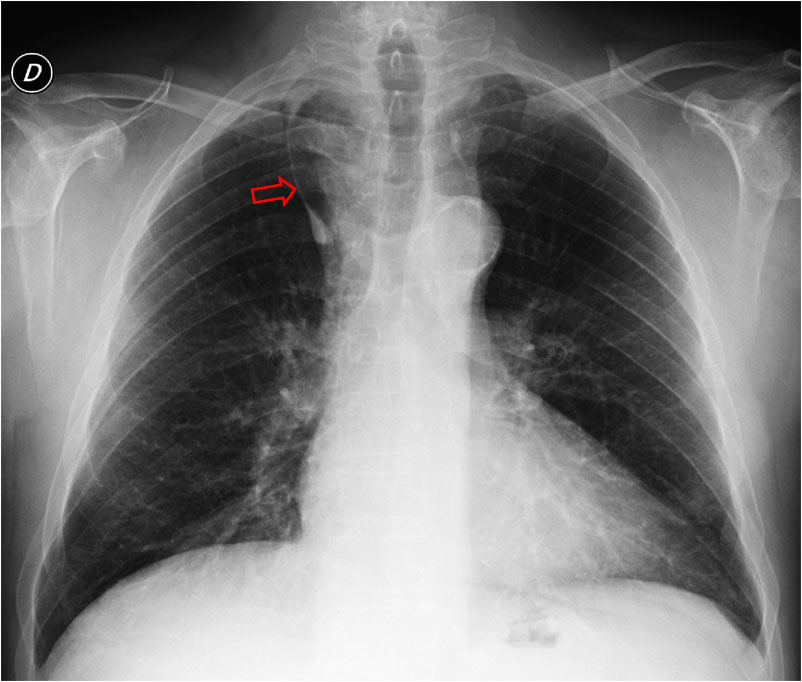

SIGNO DE LA COMA INVERTIDA

Hallazgo en la radiografía posteroanterior de tórax que consiste en una línea fina radiodensa y curva que surca verticalmente el campo superior del pulmón derecho y acaba en una densidad ovalada situada por encima de la salida del bronquio lobar superior derecho. La densidad corresponde a la vena ácigos y la línea a la cisura accesoria que delimita el lóbulo de la ácigos. Ambas densidades forman una coma invertida. Se trata de una variante anatómica relativamente frecuente, visible en una de cada 200 radiografías aproximadamente.